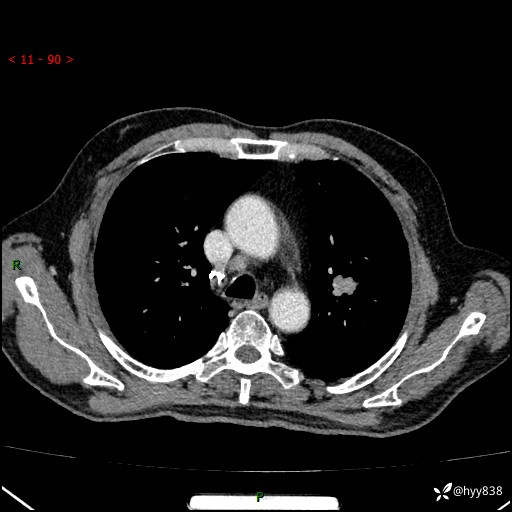

辅助检查:CT

增强